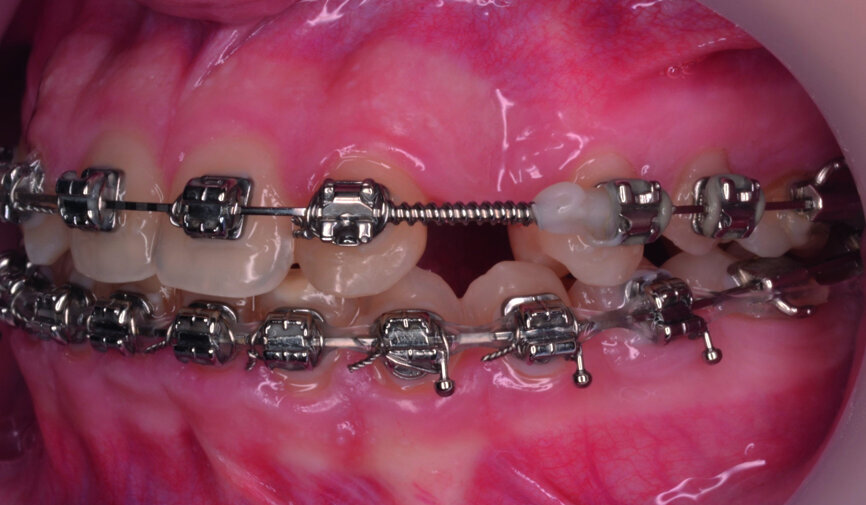

- Upper bracket placement (Fig. 22): level and align the gingival margins, and correct the torque on the upper canines who will substitute the lateral incisors.

- Implants space opening: substitute laterals with canines (Figs. 23–25) and substitute canines with first premolars (Figs. 26–28).